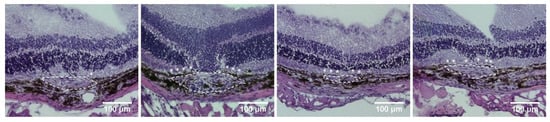

2.2. Histology, Immunofluorescence Staining, and the Effect of Hydrogen as Inhalation on the Reduction in Phosphorylation of the VEGF Receptor